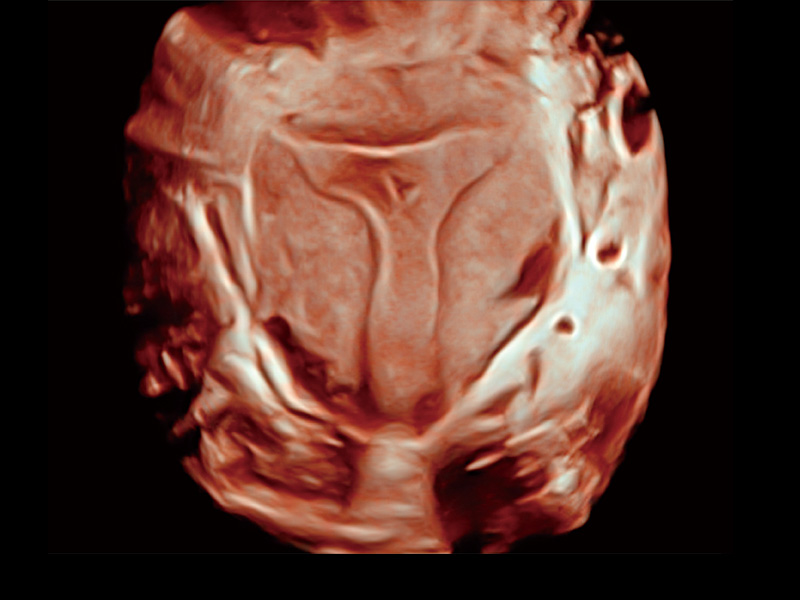

腔内三维成像技术获得显著提升,超大扇角在满足日常基础扫查的同时,支持卵泡自动测量及多种三维渲染模式,为您提供更多的诊断信息,尤其是在子宫畸形的诊断,内膜及肿瘤占位观测中起到了重要的作用。

单角子宫

输卵管间质部妊娠